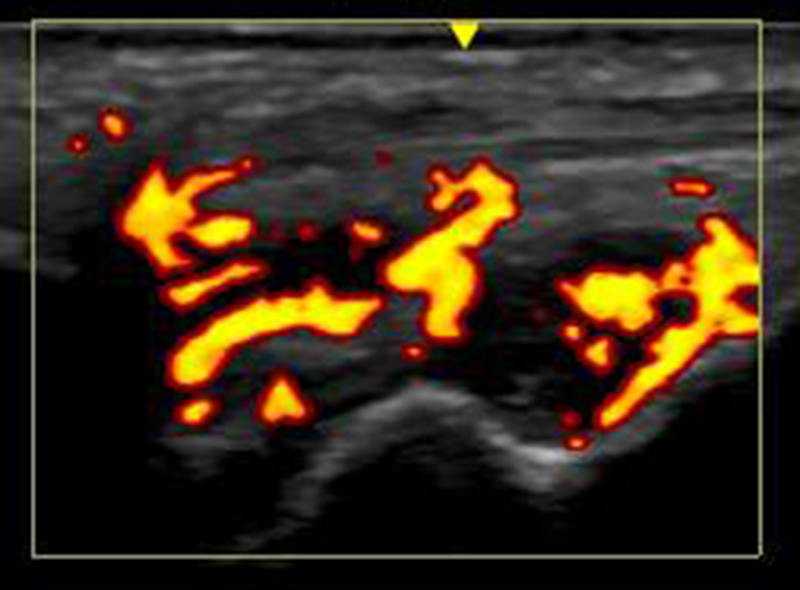

超音波診断装置

X線では評価しにくい筋肉や靭帯などを詳細に描出する、身体に優しい診断装置です。

関節のケガの場合には患部を動かしながら評価できるところも特徴です。

関節リウマチでは患部の炎症を評価する場合に有効です。

また、軟部腫瘍(できもの)の評価にも力を発揮します。

超音波検査画像

リウマチ